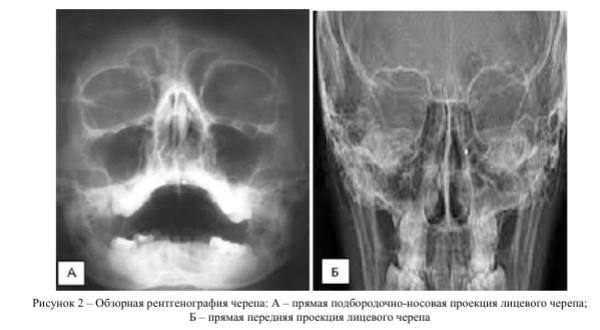

Всем пациентам проводили съемку черепа в передней прямой и боковой проекциях на рентгеновском аппарате «Униэксперт 3+» фирмы Ада- ни. Режимы работы 75 кВ, 32 мА^ ПФР 115 и эффективная доза 0,05 мЗв.

Рентгеновское исследование использовали в рамках первичной диагностики для визуализации костно-травматических изменений лицевого скелета, оценки изменений конфигурации стенок орбит, околоносовых синусов, носовой полости, видимых линий переломов. Косвенно оценивали мягкие ткани лицевого скелета при отёке мягких тканей или наличия вакуолей воздуха [7, 8].

При обследовании на дооперационном этапе всем пациентам (n=108; 100%) проводили анализ данных методов лучевой диагностики - обзорной рентгенографии, мультиспиральной компьютерной томографии согласно разработанному и расширенному протоколу описания повреждений костных и мягкотканных структур средней зоны лица.

Рентгенологическое исследование данной области позволило оценить нарушение целостности костей по следующим признакам: видимая линия перелома, нарушение гладкости контура кости и расхождение отломков костей в скулолобной (п=53; 49,1%), подглазничной (п=54; 50%), скулоальвеолярной областях (п=50; 46,3%). Увеличение объёма травмированной орбиты отметили в 32 случаях (29,6%). Также встречались косвенные признаки травматических повреждений средней зоны лица: затемнение верхнечелюстного синуса на стороне травматического воздействия (п=58; 53,7%) и в области мягких тканей средней зоны лица (п=56; 51,9%). Признаки инородных тел средней зоны лица и орбиты отметили у 10 пациентов (9,3%).

Детальную информацию о состоянии мягких тканей орбиты при использовании рентгенологического метода получить не удалось (рис. 2).